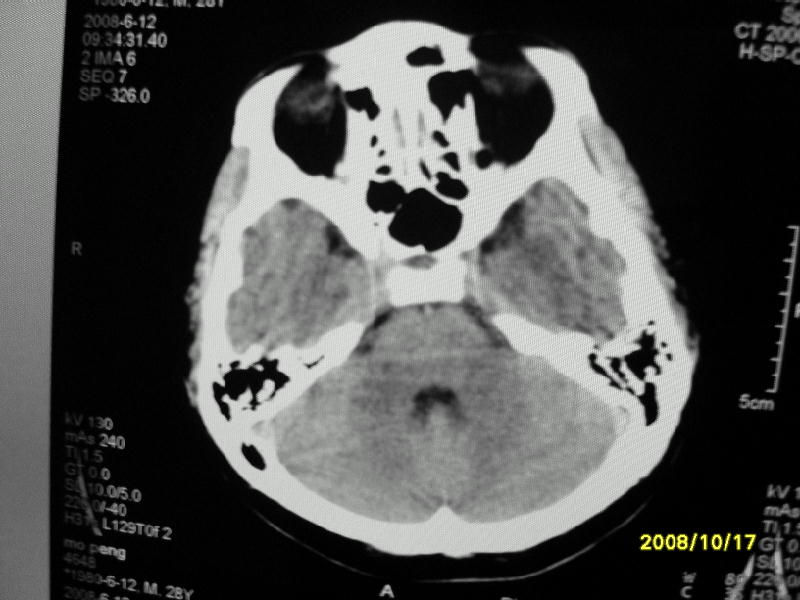

检查名称:     ct颅脑平扫           男     28岁

表现:左顶叶见斑点状致密影。边缘清,大小约0。3*1。0cm,余脑实质密度及灰白质结构示见异常。脑室系统大小,形态,密度未见异常。脑沟。脑裂。脑池未见异常密度影。中线结构无移位。

印象:左顶叶少许钙化灶